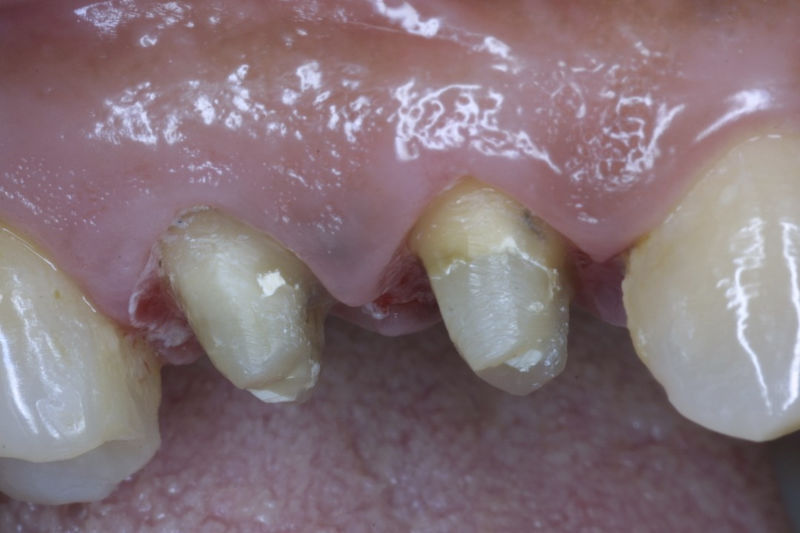

Restauraciones fabricadas en el laboratorio con materiales estéticos, los cuales cubren de manera total dientes anteriores y posteriores. Se utilizan primariamente para restaurar dientes con caries, fracturas y/o defectos amplios, así como soportes de puentes. Para poder enviar el caso al laboratorio se toman impresiones utilizando materiales de impresión o técnicas modernas digitales.

Son aditamentos artificiales colocados en la parte interna de la raíz de dientes con tratamiento endodóntico y con amplia destrucción. Usados comúnmente para soportar coronas completas.